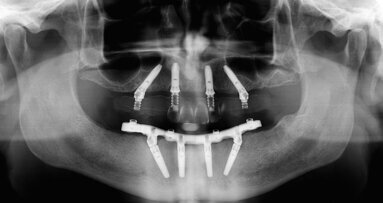

Several factors are involved in the achievement of implant primary stability, such as the insertion torque, the implant’s macrogeometry, the surgical technique, and the bone quality and quantity. Implant primary stability is considered one of the key factors for osseointegration and is associated with insertion torque. Several studies have suggested that insertion torque values of 25–45 N cm could prevent micromovements that could impair the bone healing around the implants. The aim of the present randomized clinical trial was to evaluate and compare the clinical outcome for implants placed with a high insertion torque (50–100 N cm) and a regular insertion torque (within 50 N cm) in healed ridges after two years.

Patients requiring implant therapy to replace missing teeth without the need for bone augmentation at the time of implant placement were selected for this study. All of the patients were divided according to a randomization list into two groups: high insertion torque (CT implants inserted with insertion torque ≥ 50 N cm) and regular insertion torque (Blossom CT implants with insertion torque < 50 N cm). The implants were left to heal submerged for three months and then restored with individualized abutments and cemented metal–ceramic crowns. Variables registered were insertion torque values, thickness of the buccal bone plate after implant osteotomy preparation, marginal bone level and facial soft-tissue level. All of the patients were followed for two years after implant placement, with recall visits at three, six, 12 and 24 months.

116 implants were placed: 58 implants were allocated to each group, with mean insertion torque ranging from 20 N cm to 50 N cm for regular insertion torque and from 50 N cm to 100 N cm for high insertion torque. Three implants failed. Two implants showed at the 12-months evaluation a marginal bone loss > 1.5 mm and were thus considered unsuccessful.

Implants inserted with a high insertion torque in healed bone ridges showed more periimplant bone remodeling and facial soft-tissue recession than implants inserted with regular insertion torque after two years, both in the maxilla and in the mandible. The findings suggest that the clinician should pay attention to several factors in implant therapy, such as the thickness of the buccal bone, the corticalization of the surgical site, the implant’s macrogeometry and the potential influence of insertion torque on implant therapy outcomes.